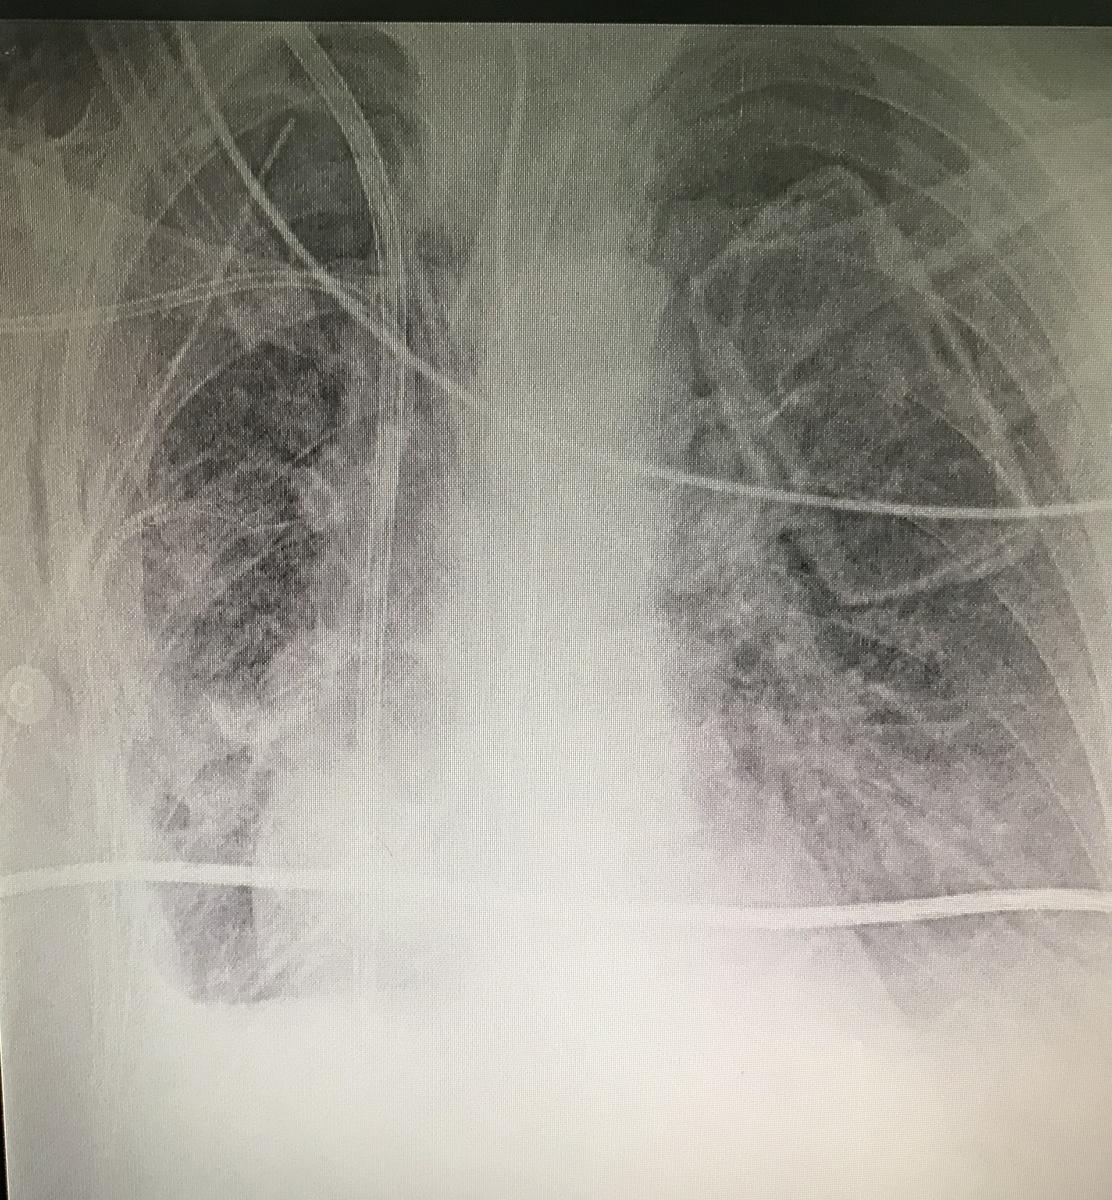

It is decided together with the patient, relatives, and oncology, the surgical behavior to achieve complete extirpation or the greatest possible resection. Videofibrobronchoscopy was performed first, without evidence of endobronchial lesions. The authors continued with a wide right thoracotomy. Complete resection of the tumor was achieved, along with fragment of diaphragm and pulmonary parenchyma. The tumor was approximately 1.5 kg, compatible with low-grade leiomyosarcomade, with lesion-free resection margins (figure 4). The patient achieved good pulmonary expansion in the immediate postoperative period (figure 5). She recovered in the intensive care unit at the beginning, and then continued in the general ward, with good evolution.